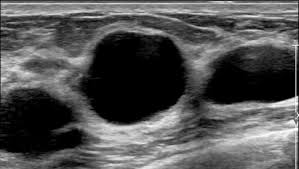

It is less accurate in detecting malignancy 44,45. Tumor margin is the most important sonographic feature in evaluating breast lesions in any size group. Ultrasound can usually help differentiate between benign and malignant tumours based on shape, location, and a number of other … 14.11.2018 · breast ultrasound cancer vs benign breast ultrasound can help in diagnosis in differentiating between benign and malignant tumors, often without the need for a … 01.06.2014 · there was very little other pathology in either benign or malignant groups.

21.09.2018 · differentiating ovarian cyst vs. Tumor margin is the most important sonographic feature in evaluating breast lesions in any size group. 14.11.2018 · breast ultrasound cancer vs benign breast ultrasound can help in diagnosis in differentiating between benign and malignant tumors, often without the need for a … Ultrasound can usually help differentiate between benign and malignant tumours based on shape, location, and a number of other … It is less accurate in detecting malignancy 44,45. 01.06.2014 · there was very little other pathology in either benign or malignant groups. Ovarian cancer on 3d ultrasound. Ultrasound is most reliable predicting that an ovarian lesion is benign;